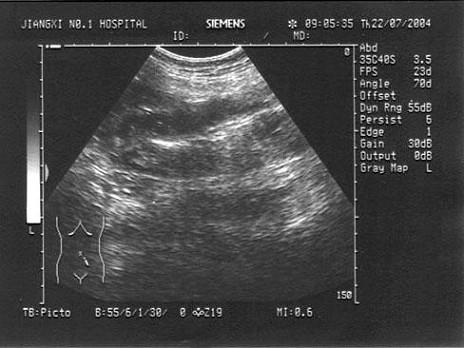

问题 男,60岁,便血就诊。PE:左下腹可扪及一肿块,质硬。结合超声声像图,诊断为?(?)

选项 A.Crohn's病 B.肠梗阻 C.肠癌 D.肠套叠 E.肠结核

答案 C